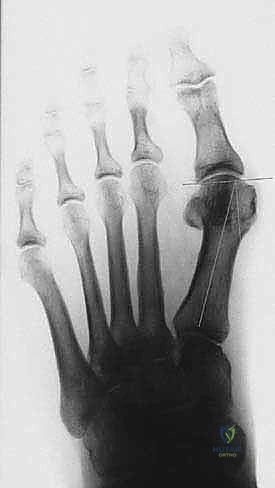

يقوم الدكتور هطيف بقياس زوايا محددة:

* زاوية إبهام القدم الأروح (HVA): الزاوية بين عظم المشط الأول والإصبع الكبير.

* الزاوية بين الأمشاط (IMA): الزاوية بين عظم المشط الأول والثاني.

بناءً على هذه الزوايا، يتم تصنيف الحالة إلى خفيفة، متوسطة، أو شديدة. جراحة (ماو) تُخصص عادة للحالات المتوسطة إلى الشديدة التي تتطلب تصحيحاً كبيراً ومستقراً.